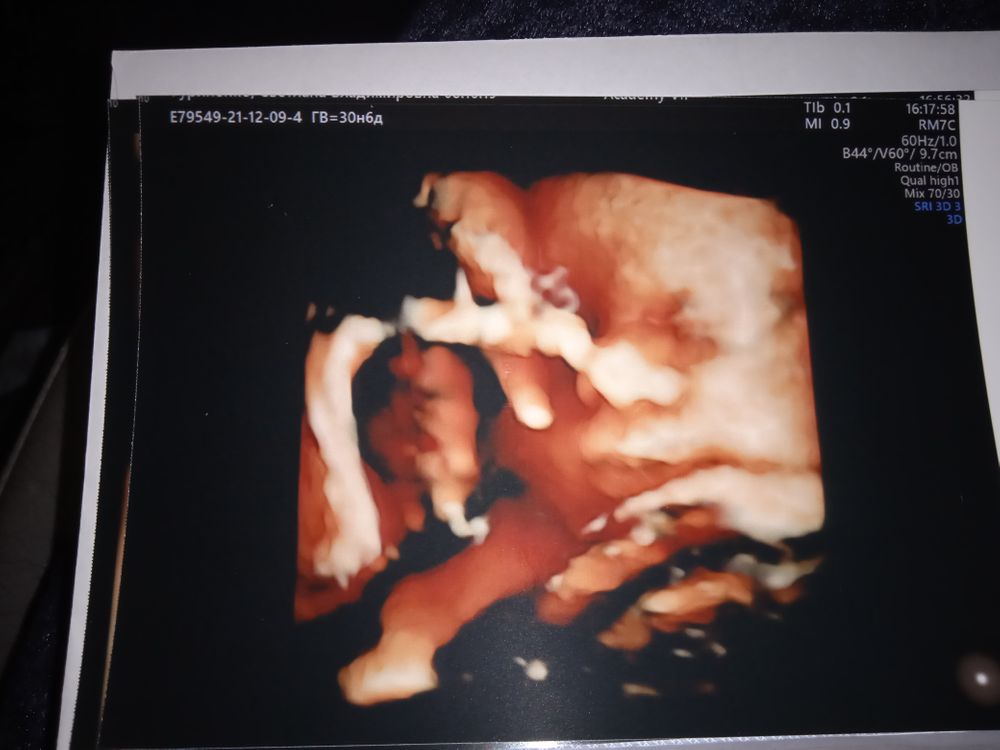

Лучше всего личико видно, когда ещё много околоплодных вод, 21-23 недели должно быть ещё норм. Я не помню, на каком сроке прошлый раз была, но вот в 31 неделю уже толком не посмотришь, т.к. тесновато, у него то ручки перед лицом, то пуповина, то в матку упёрся мордашкой

Почти 31 неделька и 21 неделька